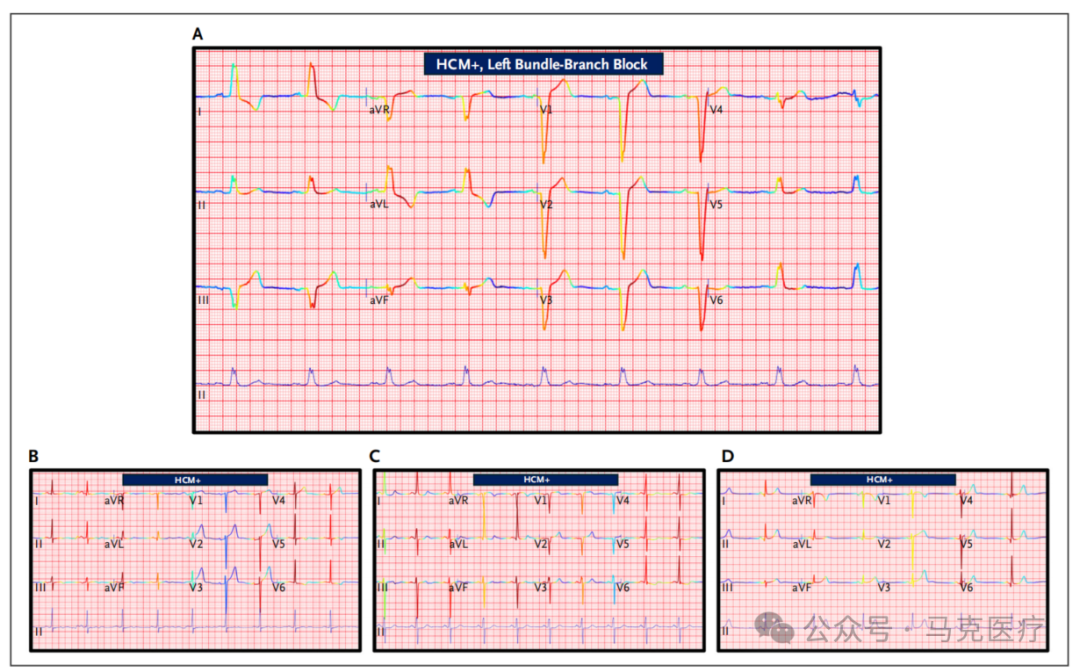

图片

图4未校准和校准模型排序对患者病例排序的并置